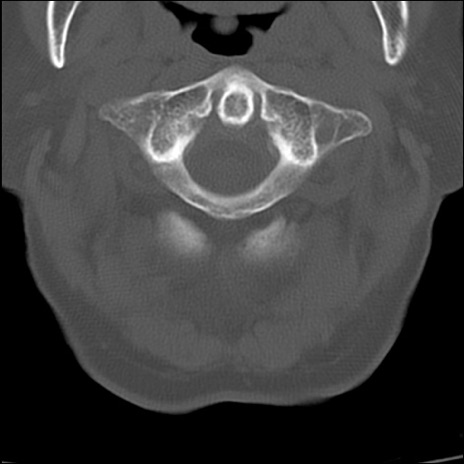

症例48 頚椎CT(横断像)

頚椎CT